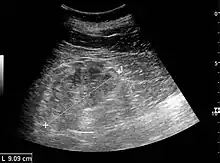

Renal ultrasonography of chronic renal disease caused by glomerulonephritis with increased echogenicity and reduced cortical thickness. Measurement of kidney length on the US image is illustrated by '+' and a dashed line.[10]

Some forms of glomerulonephritis are diagnosed clinically, based on findings on history and examination. Other tests may include:[9]